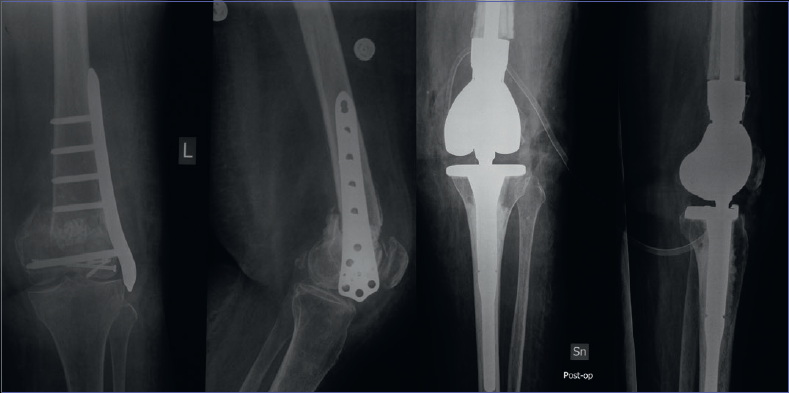

The management of proximal femur nonunions in elderly patients has evolved over the years. Aging induces a loss of bone regenerative capacity 9, and as a consequence techniques commonly used in young patients such as Masquelet or bone transport are burdened by a high rate of failure. Before the introduction of megaprostheses, the main solutions were the Gilderstone procedure or, in extreme cases, disarticulation, which are both very disabling for the patient. Several authors have published their findings related to management of non-neoplastic conditions by proximal femoral replacement with megaprosthesis. In 2012, Dean et al. 10 published the results of their study on 8 patients with failed internal fixation for traumatic proximal femoral fractures treated with PFR with endoprosthesis. The procedure was carried out as a one-stage procedure in six cases and a two-stage procedure in two cases of infected nonunion. No post-operative complications were reported, clinical outcomes were satisfactory (mean Harris Hip Score was 71.4 at final follow-up), and immediate weight bearing was allowed. The authors defined PFR as an effective salvage procedure in these difficult cases (Fig. 1). Parvizi et al. reported a dislocation rate of 19% in their study of 48 PFRs 11. The prosthetic survival rate was 87% at one year, 82% at three years, and 73% at five years. The authors concluded that a prerequisite for successful PFR is to restore the correct anatomy and biomechanics of the hip and that the length of the distal part of the femur be adequate to obtain secure fixation of the femoral stem.

Figure 1.Proximal femur nonunion treated with modular endoprosthesis. A) pre-operative x-rays; B) post-operative x-rays.